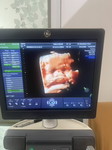

อยากถามแม่ๆค่ะ ตอนนี่32สัปดาห์แล้วค่ะน้องไม่ยอมกับหัว แถมน้ำหนักไปถึง 2,000 แล้วค่ะ หมอบอกน้องใหญ่ไป มีแม่ๆบ้านไหนมีวิธีให้น้องกับหัวไหมค่ะ ไม่อยากโดนผ่าเลยค่ะ #แม่มือใหม่ #ท้องแรก #ใกล้ๆความจริงขึ้นทุกวัน

บ้านนี้เดินทำงานบ้านทั้งวันเดินจนเท้าฟอง เดินจนท้องปั้นแข็งหลายครั้ง จนหมอให้ยาคลายมดลูกบีบตัวมากิน40เม็ดจนกว่าจะได้ซาวด์ใใหม่ บ้านนี้อยู่ท่าก้นยังไงก็อยู่ท่าเดิมมาเดือนกว่าๆแล้วค่ะ ตอนนี้35+3แล้ว น้ำหนักน้อง 2437กรัม หมอบอกว่าถ้า37+3วีคไปอัลตร้าซาวด์ที่โรงพยาบาล ถ้ายังไม่กลับหัว ก็เตรียมผ่าคลอดตอน38สัปดาห์เลยค่ะ